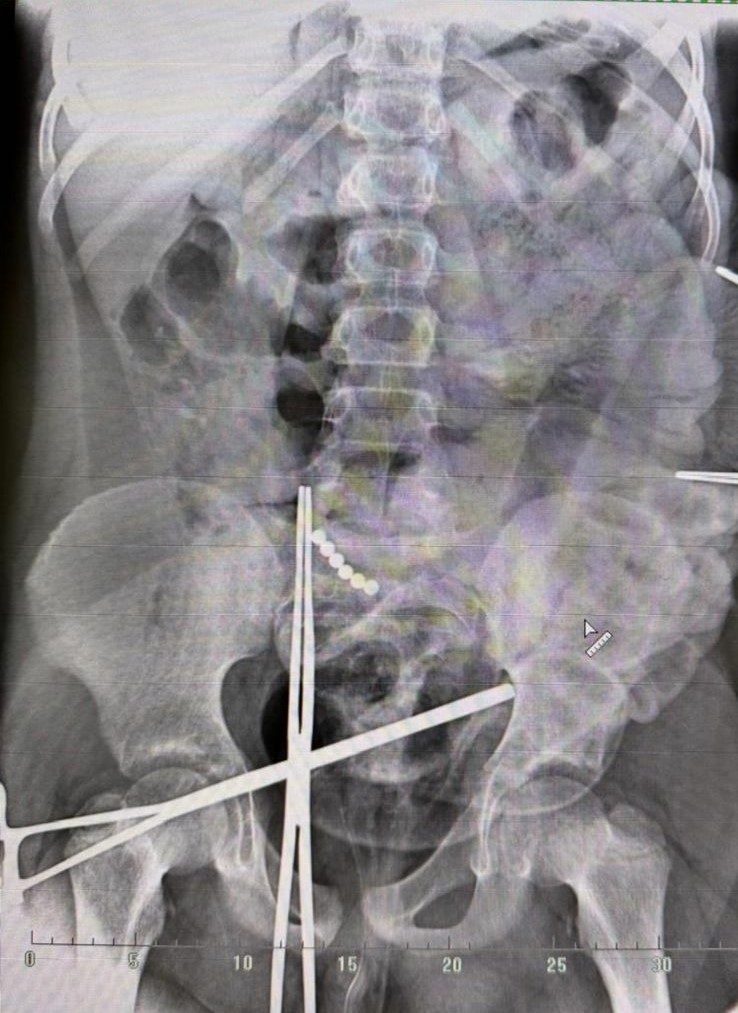

10-летний мальчик проглотил 19 (!) магнитных шариков. Никому об этом не сказал. А через месяц поступил в ГБУ РО «ОДКБ» с клиникой перитонита. Его экстренно прооперировали. Операция начиналась лапароскопически, но в ходе операции пришлось перейти на лапаротомию (открытая операция). Хирурги удалили все инородные тела, разобщили множественные межкишечные свищи, которые привели к перфорации (прободению) тонкой кишки, и ушили их.